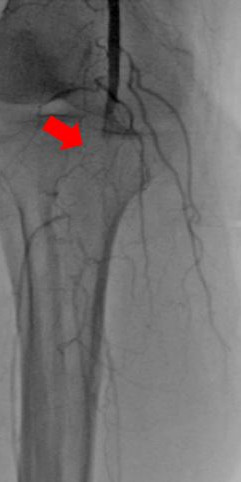

術(shù)中DSA:箭頭提示雙髂動(dòng)脈血栓栓塞,血流中斷

術(shù)中DSA:雙髂動(dòng)脈血流恢復(fù)